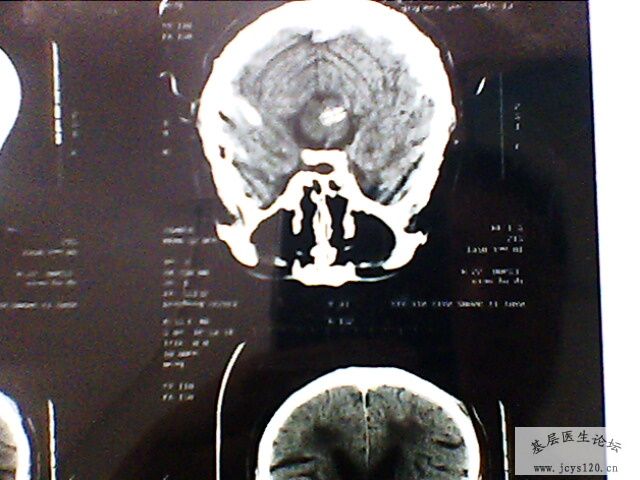

辅助检查:急诊颅脑CT:桥脑处见一卵圆形高密度灶,最大直径1.0cm,右基底节处见多个不足1.0cm大小的低密度灶,侧脑室前后角分布均匀的低密度灶,脑室及脑沟裂未见异常,中线结构居中。 CT意见:脑血肿 皮质下动脉硬化性脑病

CT片子已经上传,患者目前正在住院治疗中.......... 目前处方: 甘露醇 125 ml 静滴 BID 5%GNS 250 ml 头孢哌酮钠舒巴坦钠 3.0 5%GS 250 ml 脑复康 5.0 胞二磷胆碱 0.75 患者目前病情稳定,血压正常,无 头痛头晕,饮食睡眠可。 想和大家探讨下,该患者下一步活血化瘀药物的使用!这时候使用丹参等活血化瘀的药物应该掌握的适应症和注意事项?请大家分析一下!

病情跟踪报道: 患者今天是输液第十天,瞩患者复查CT,见附件! 患者目前一般情况好,饮食睡眠正常,无头痛头晕,上唇仍感麻木,四肢活动正常,肌力正常,右侧胸痛减轻。病人及家属对治疗比较满意,目前还在继续治疗中 目前输液处方: 5% GS 250 ml 丹参 400mg 5%GS 250 ml 脑复康 5.0 胞二磷胆碱 0.75 门冬 10ml

从患者CT上大家应该可以看出,建议大家对比一下患者发病时的CT片子,桥脑部位的出血(高密度)现在密度降低,上级医院CT诊断为出血吸收期,所以患者目前正在恢复当中!!!!